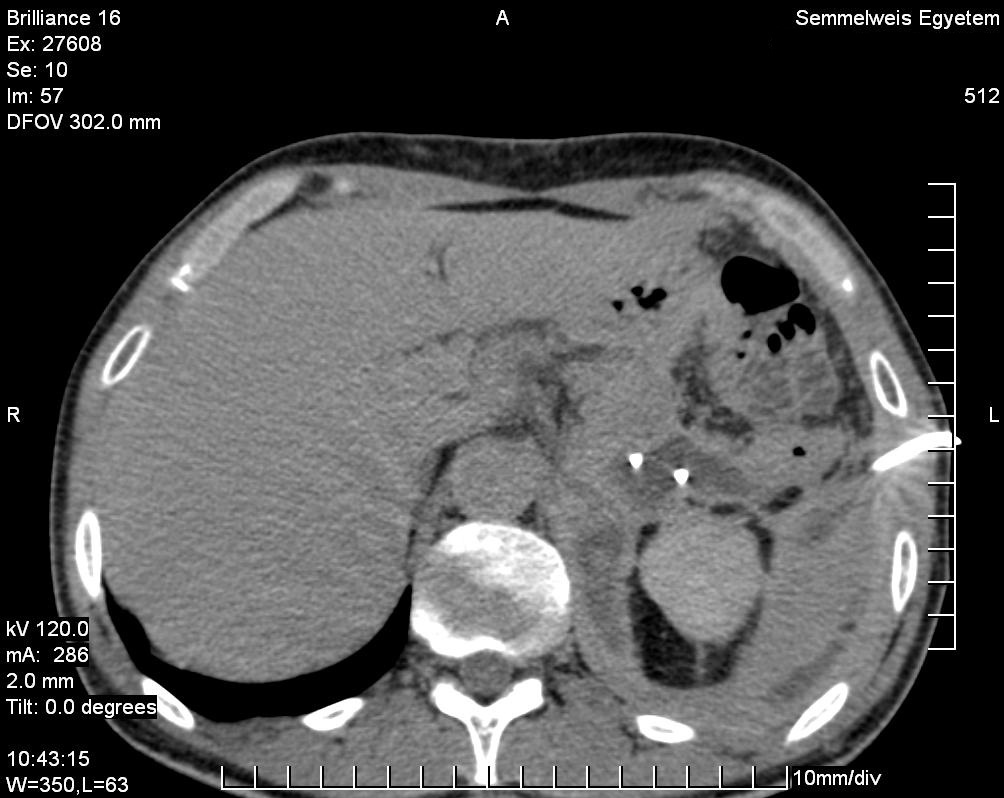

The simple cyst (Figure 16) indicates a difference from the multicystic liver only in the number of the cysts. Conversely, the polycystic liver (Figure 17) is an autosomal dominant inheritant disorder, in which the cystic conversion can be present in up to 70-80% of the liver parenchyma due to the large number of the cysts. It often accompanies with polycystic kidneys, whilst the entire polycystic syndrome – if also polycystic affection of the pancreas is also associated – occurs very rarely.

Figure 17: Polycystic liver, contrast enhanced CT